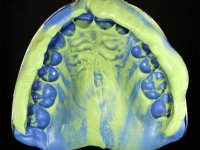

To define the dental zone to be covered by the Maryland bridge retainers, the patient was asked to perform maximum intercuspidation movements, and the contact points were marked with articular paper. Tooth preparation of the interproximal surfaces was made, to create a prosthetic insertion axis. It was sought that the mesio-distal diameter at the incisal level was equal to the diameter mesio-distal at the cervical level, that is to say, the interproximal walls were parallelized. Tooth preparation was done with fine grain diamond drills, and later polishing was done with abrasive discs. Color information was collected even before confection of the impression, to avoid dehydration of the arcade. Definitive impression was made using wash technique impression with silicone of heavy and regular consistency, both with fast setting, and a working plaster model was prepared in the lab. A laboratory scanner was used to scan the working model, and later, the infrastructure for the Maryland bridge was made using a CAD-CAM process. Ceramic was placed on this subframe. A ceramic adhesive was applied to the internal surface of the wings and connectors, which would enable bonding to the adjacent teeth. The adhesive bridge was bonded in the mouth following the conventional bonding technique. After bonding, the protrusion and laterality movements were carefully checked to avoid undesirable contacts.